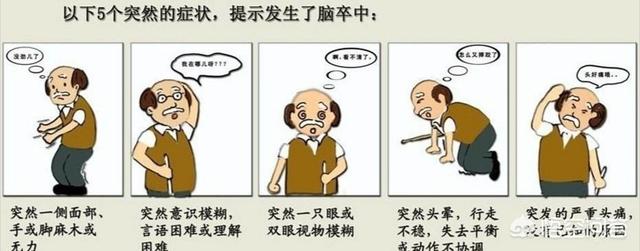

Quelles sont les manifestations de l'AIT ?

1) Perte de conscience soudaine. Tout d'un coup, vous ne savez plus rien, vos yeux deviennent noirs, vous vous évanouissez, puis vous vous sentez bien.

2. apparition soudaine d'une faiblesse et d'un engourdissement des membres. Par exemple, tout d'un coup, le pied est faible, on ne le sent plus, on ne peut plus se tenir debout. Ou bien, tout à coup, vos mains sont faibles et vous ne pouvez rien tenir, mais vous vous en remettrez au bout d'un moment.

3. cécité soudaine d'un œil, incapacité de voir.

4. une sensation soudaine d'engourdissement de la langue, un manque de clarté dans l'élocution. Ou incapacité soudaine à parler.

5. des vertiges soudains, une démarche instable, la vision de choses qui tournent autour de vous

6. incapacité soudaine à entendre les choses.

Ces symptômes disparaissent généralement en 30 minutes, mais il est important de ne pas les prendre à la légère, surtout s'ils sont récurrents ou si vous faites partie d'un groupe où l'incidence des infarctus cérébraux est élevée.